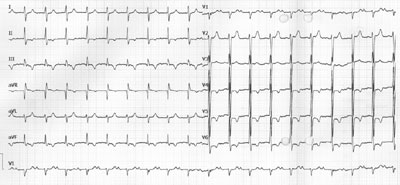

EKG-Quiz 54

Ein 89-jähriger Mann meldet sich mit stundenlangem Herzjagen und Unwohlgefühl. Sein Blutdruckmessgerät hat zuhause einen Puls von 140/min angegeben.

Wegen einer Synkope bei einem Sick-Sinus-Syndrom mit Bradyarrhythmien (Sinusknotenstillstände, Bradykardien bis minimal 26/min) hat er vor 16 Monaten ein ventrikuläres 1-Kammer-Schrittmachersystem erhalten: Betriebsart VVIR, Interventionsfrequenz 50/min, maximale Sensorfrequenz 120/min.

Bekannt ist eine langjährige arterielle Hypertonie und eine koronare 3-Gefässerkrankung mit operativer Myokardrevaskularisation 1999 und später 2 Mal PTCA mit Stenting. Daneben besteht ein Diabetes mellitus Typ 2 und eine chronische Niereninsuffizienz (Serum-Kreatinin 180 µmol/l).

Aktuelle Therapie: Aspirin 100 mg 1-0-0, Atacand plus 1-0-1, Rasilez 300 mg 1-0-0, Torem 10 mg 1-0-0, Nebilet 5 mg 2-0-0, Sortis 20 mg 0-0-1, Insulin.

Ruhe EKG

Wie würden Sie den Rhythmus in diesem Ruhe-EKG am ehesten beschreiben?